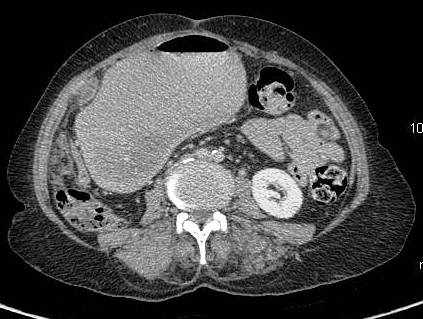

Association with cholelithiasis

Etiology of gallbladder cancer remains obscure although cholelithiasis (Figure 4,5) [3-5], cholecystitis [12], racial and ethnic factors, blood groups, carcinogens, lipid peroxidation products, benign tumors, and secondary bile acids have been implicated as possible causes [13-15].

Figure 4: Gallbladder shows multiple hyperdense incarcerated calculi with loss of normal tissue planes. Gross ascites noted with peritoneal enhancement.